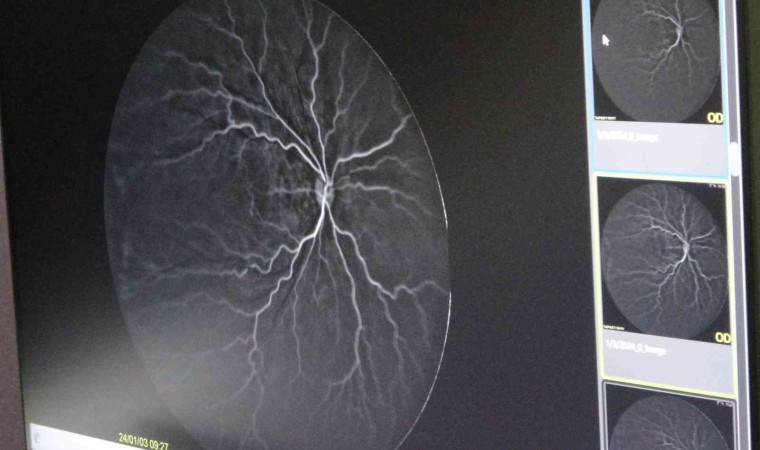

ROP tedavisi olan bebeklerde özellikle gözde retina damar gelişiminin çok önemli bir husus olduğunu değinen Ekinci, “Çünkü birçok bebekte damar gelişimi zayıf kalıp tekrar hastalığın nüksüne sebep olabilmekte. Bunu tespit edebilmek için son yıllarda tüm dünyada ve ülkemizde bazı merkezlerde göz anjiyografisi kullanılmakta. Anjiyografiyi biz genel anestezi altında uygulamaktayız. Damardan boyalı bir madde vererek gözün arkasındaki damarların gelişimini tespit etmekteyiz. Anjiyo sonucuna göre tedavi kararımızı veriyoruz. Bebekte eğer damar gelişimi eksikse veya damarlarda bizim gözümüzle göremediğimiz sızıntılar varsa lazer tedavisiyle bebeğin gözünü emniyete almış oluyoruz” diye konuştu.

Daha önce Diyarbakır’da bu sorunu tespit ettikleri bebekleri İstanbul ya da Ankara’ya sevk etmek durumunda kaldıklarını, şimdi ise cihazın olmasıyla hastaları il dışına göndermeye gerek duymadan tedavi ettiklerini ifade eden Ekinci, “Son birkaç aydır artık bizim merkezimizde de cihaz var. Bebeklerimizi il dışına göndermeden görüntülerini çekip tedavilerini yapabilmekteyiz. Anjiyo cihazının bir diğer güzel yanı sadece ROP değil, diğer retina hastalıklarında da kullanabiliyoruz” ifadelerine yer verdi.